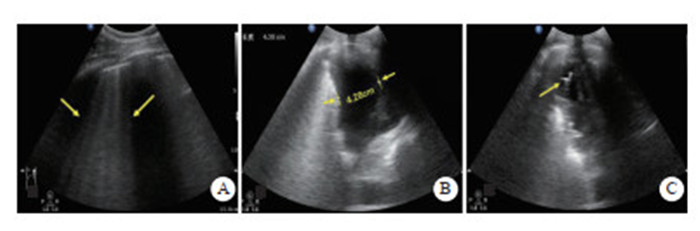

(2)血胸:如坐位扫查,仅肋膈角被无回声积液充填,为少量积液;如任意体位胸腔均可见液性暗区,为中-大量积液,超声对其诊断准确性100%[39](图 7-B)。

2.3.3 检查方法采用BLUE法中的检查位置(见图 7)。共6个检查点:(1)上BLUE点位于上面手的中央(左侧、右侧共2个);(2)下BLUE点位于下面手掌的中央(左侧、右侧共2个)。这四个点遵循肺部解剖,尽可能避开了心脏;(3)后侧肺泡或胸膜综合征点(posterolateral alveolar and/or pleural syndrome point, PLAPS)位于下蓝点延长线与腋后线相垂直的交点;(4)膈肌点(diaphragmatic point)位于下蓝手小指外侧缘即膈肌线,其延长线与腋中线交点。检查时间一般不超过3 min。

检查时间一般不超过3 min。

| A: 上蓝点(2个)、下蓝点(2个);B:PLAPS点(黄箭)、膈肌点(蓝箭) 图 7 BLUE法定位扫查 |